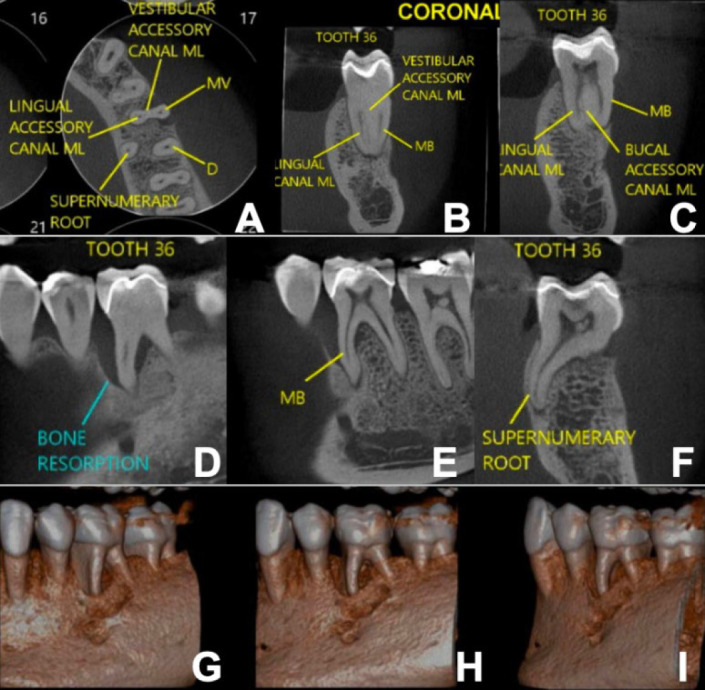

本病例报告强调了Biodentine作为一种孔内屏障的创新应用,用于治疗牙周内病变伴牙根延伸的牙裂。一名37岁女性患者报告咀嚼第36颗牙齿时疼痛。中牙根周围有明显的牙周附着物丧失。牙齿被诊断为牙髓坏死。在根管通道上,观察到一个垂直的裂缝延伸到中管壁。使用旋转器械确定和塑造根管。放置氢氧化钙作为管内敷料。一周后,患者无炎症症状返回。根管内填充了杜仲胶和生物陶瓷水泥。在孔口外2.0 mm处应用生物牙牙素修复水泥来密封和加固该区域。采用复合树脂修复根管通道腔。12个月的临床和影像学随访显示明显的根尖周愈合和无炎症体征。48个月的x线摄影和计算机断层扫描证实了骨修复和牙齿功能的持续。Biodentine的孔内屏障显示出显著的有效性,与文献中关于其益处的报道一致。该方案结合现代技术和及时修复,在处理牙根延伸的牙裂,加强复杂病例的牙齿保存方面显示出希望。

This case report highlights the innovative application of Biodentine as an intraorifice barrier in the management of cracked teeth with radicular extension associated with endo-periodontal lesions. A 37-year-old female patient reported pain during chewing on tooth #36. Significant periodontal attachment loss was noted around the mesial root. The tooth was diagnosed with pulp necrosis. Upon endodontic access, a vertical crack extending into the mesial canal walls was observed. Root canals were identified and shaped using rotary instruments. Calcium hydroxide was placed as an intracanal dressing. After one week, the patient returned without inflammatory signs. The root canals were filled with gutta-percha and bioceramic cement. Biodentine repair cement was applied 2.0 mm beyond the orifice to seal and reinforce the area. The endodontic access cavity was restored with composite resin. Clinical and radiographic follow-ups at 12 months revealed significant periapical healing and the absence of inflammatory signs. A radiographic and computed tomography scan at 48 months confirmed substantial bone repair and continued tooth functionality. The intraorifice barrier with Biodentine demonstrated notable effectiveness, aligning with literature on its benefits. The protocol, integrating modern techniques and timely restoration, shows promise in managing cracked teeth with root extension, enhancing tooth preservation in complex cases.